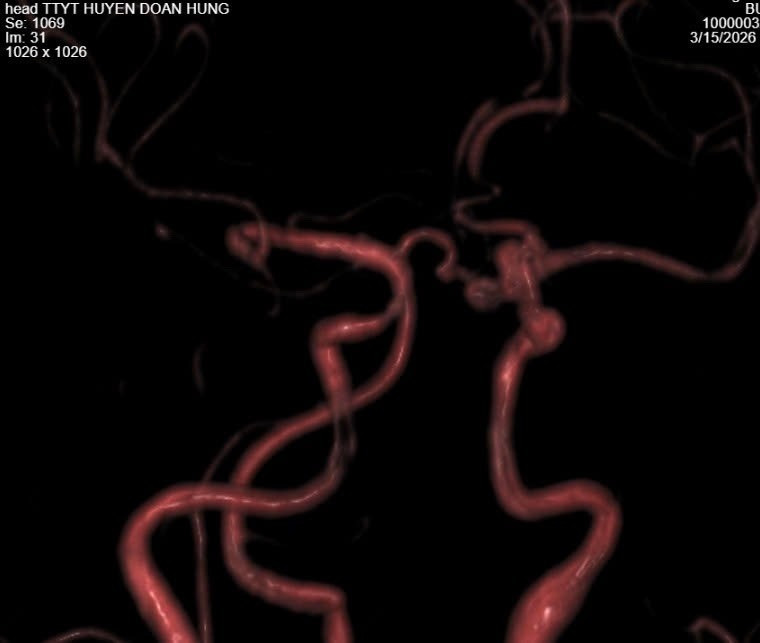

Mạch máu não bị phình - Ảnh BVCC